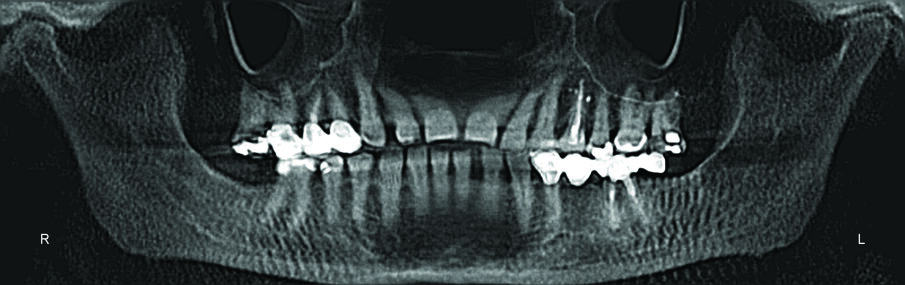

Her dental spacing was worse than her initial presentation. I feared tomographic evidence would yield condylar resorption, but her tomograms showed remarkably good condylar position with minimal lipping for an older adult patient with no anterior guidance.

Periodontal health was excellent, with no evidence of additional bone loss or resorption.